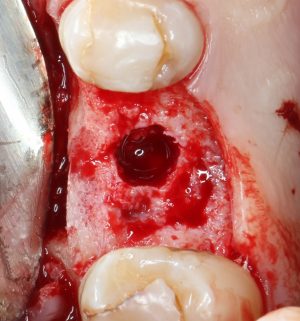

Приступаем к установке имплантата.

У имплантатов Astra Tech пипец, какая неудобная упаковка. Отчасти это компенсируется наличием ячеек, куда эти упаковки вставляются.

Кстати, комплект поставки не содержит ни заглушки, ни абатмента. А сам имплантат фиксируется на ключе простым заклиниванием платформы. Т. е. не слишком надёжно:

По этому поводу существует поговорка: «Кто не ронял имплантаты Astra Tech, тот не работал с имплантатами Astra Tech«. В общем, будьте аккуратны, в идеале, проводите все манипуляции по фиксации имплантата на ключе над столом.

Если лунка подготовлена правильно, то имплантат проваливается в неё почти полностью:

и докручивается до правильного положения несколькими оборотами.

Еще раз акцентирую внимание на том, что Astra Tech — субгингивальная имплантационная система. А это значит, что для неё выполняются те же правила позиционирования, что и для других субгингивальных имплантационных систем. Читайте здесь>>.